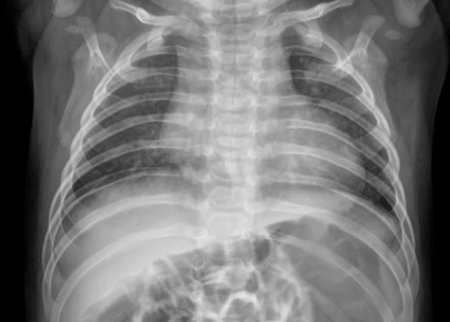

"이 포스팅은 쿠팡파트너스 활동의 일환으로이에 따른 일정액의 수수료를 제공받습니다." 이지대장체크 분변잠혈 자가검사키트, 1개입, 2개 - 기타 건강측정기 | 쿠팡현재 별점 4.8점, 리뷰 411개를 가진 이지대장체크 분변잠혈 자가검사키트, 1개입, 2개! 지금 쿠팡에서 더 저렴하고 다양한 기타 건강측정기 제품들을 확인해보세요.www.coupang.com최근 국내 연구진이 신종 인간 코로나바이러스를 발견하였다는 소식이 전해졌습니다. 이 바이러스는 기존의 코로나19와는 다른 특성을 지니고 있으며, 특히 영아에게서 발견된 사례가 주목받고 있습니다. 이번 포스트에서는 이 신종 바이러스의 발견 배경과 영아의 증상, 기존 코로나19와의 차이점, 의학적 중요성, 예방 및 치료 방법에 대해 자세히 알아보겠습니다.최근..